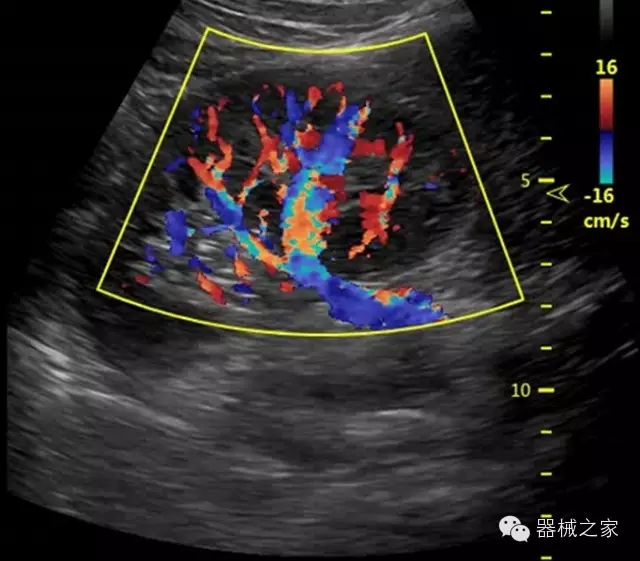

經(jīng)典產(chǎn)品:S8EXP

臨床圖片賞析

產(chǎn)品特點

·智能微血流成像技術:智能微血流捕捉技術可以提取出隱藏在背景噪聲中的弱血流信號,大大提高低速血流的敏感性;

超聲科常規(guī)領域應用

·移植S40高端臺式彩超高端平臺技術,滿足超聲科腹部、淺表、婦產(chǎn)科、心血管、肌骨等應用,提供超聲科完美解決方案;